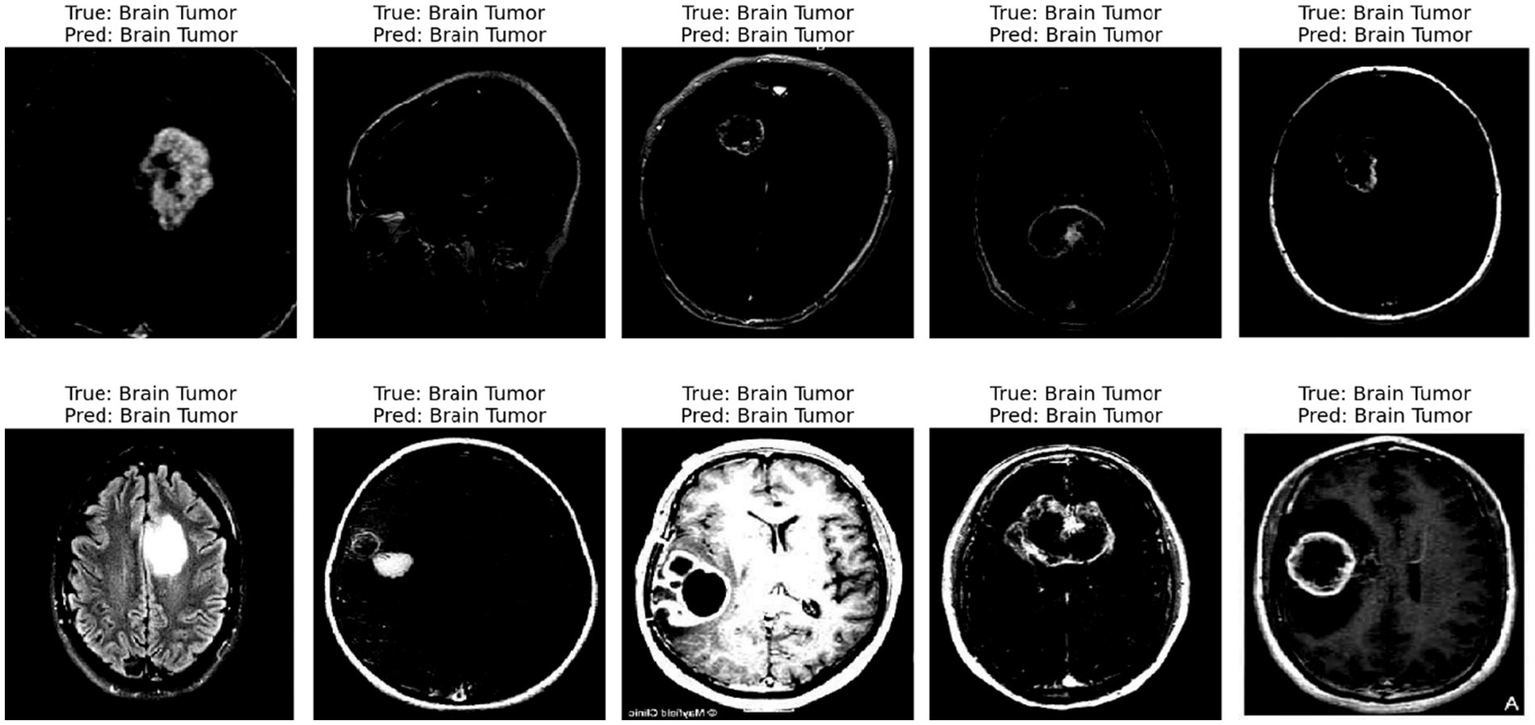

The displayed set of images (Figure 11) shows LIME (Local Interpretable Model-Agnostic Explanations) visualizations applied to five different brain scan samples, each labeled with the ground truth class “Brain Tumor.” LIME is a widely used interpretability technique that helps understand how a machine learning model arrives at a specific decision by highlighting which parts of the input image contribute most strongly to the classification (van der Velden et al., 2022; Mir and Pal, 2025).

Figure 11

LIME explanation.

In each of these grayscale brain scan images, different colored regions—primarily outlined in yellow—represent the superpixels or segmented regions that most influenced the model’s prediction toward the correct class (brain tumor). These areas are identified as being the most relevant in driving the model’s decision-making process. The gray background typically indicates less influential or neutral regions that had little or no effect on the final output.

For instance:

-

In Image 0, a visible mass is located centrally and is surrounded by highlighted regions, showing that the model focused directly on the tumor-like structure.

Image 1 shows segmentation in multiple dispersed areas, particularly near the upper and lower regions of the scan, suggesting the model has used both tumor features and possibly structural information from the surrounding brain anatomy.

Images 2 and 3 illustrate segmentation in non-central regions, but still contain some tumor-dense sections within the highlighted zones. This implies that LIME identified both relevant tumor zones and adjacent tissues as contributory.

In Image 4, the large highlighted patch precisely overlaps with a distinct tumor shape, indicating that the model heavily relied on this particular region to make its prediction.

These LIME explanations serve as a crucial tool for verifying that the model’s focus aligns with clinical expectations. For medical diagnosis tasks like brain tumor detection, it is essential to confirm that the classifier is basing its decisions on tumor-related patterns rather than irrelevant background features. LIME allows researchers and clinicians to inspect the model’s reasoning process, thereby increasing trust in its predictions and facilitating model transparency.